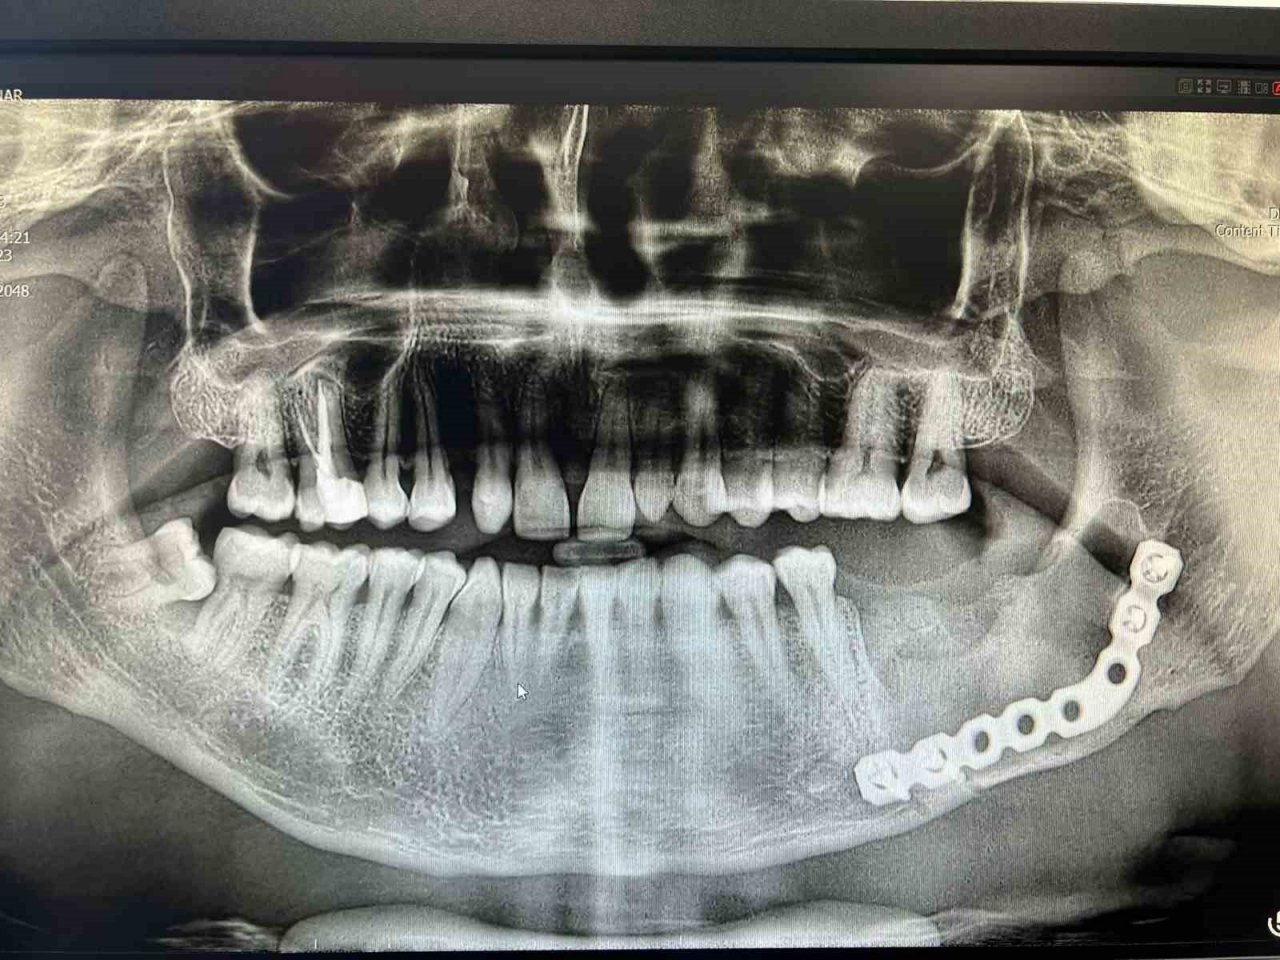

37 numaralı dişi çekilen hastanın tomografi görüntüleri çekildi. Hastanın 3D yazıcı sistemi ile çene modeli oluşturuldu. Oluşturulan 3D çene modeli üzerinde metal plak denemesi yapıldı. Denemenin ardından Ağız, Diş ve Çene Cerrahisi Uzmanı Yunus Balel, genel anestezi altında hastayı ameliyat ederek metal plak işlemini hastaya uyguladı.